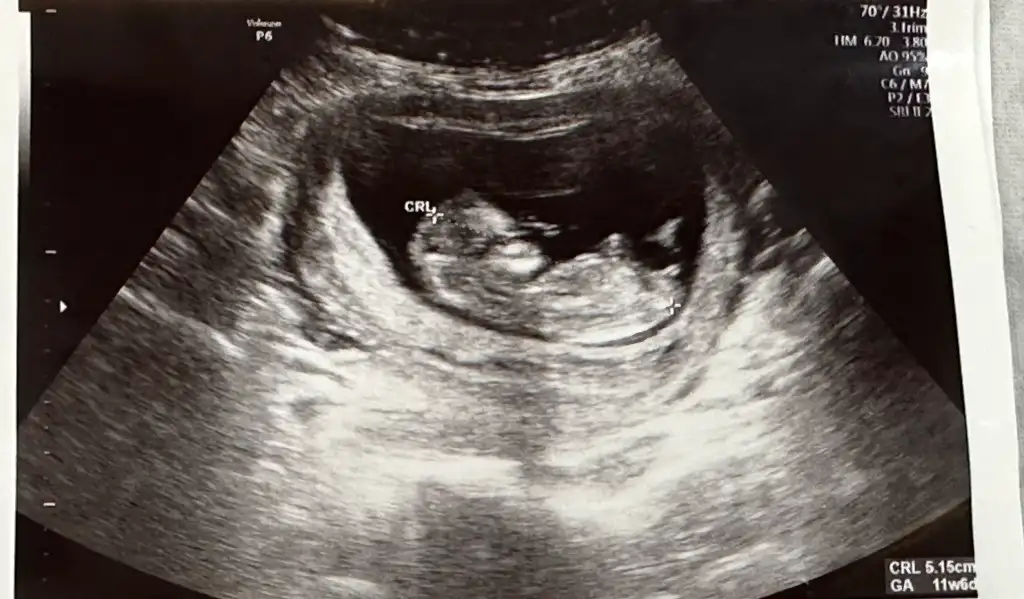

Yorum yaparmısınız. Biri 11hafta 6günlük. Diger 16 haftaKızzzz

kızYorum yaparmısınız. Biri 11hafta 6günlük. Diger 16 hafta

Erkek gibi geldi banaYorum yaparmısınız. Biri 11hafta 6günlük. Diger 16 hafta

Sizinde erkek

Erkek :) givi duruyor ama Allah gönlünüzdekini versinYorum yaparmısınız. Biri 11hafta 6günlük. Diger 16 hafta